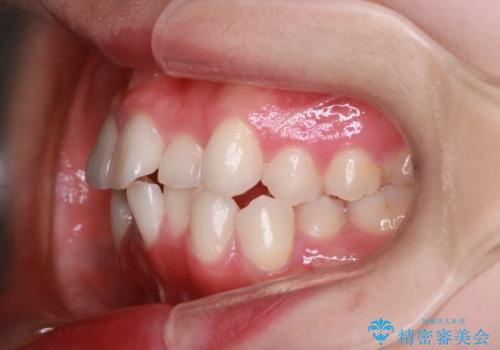

【抜歯インビザ】前歯の凸凹をなおしたい

- 前歯の凸凹を主訴に来院されました。

前歯はあまり下げる必要がなかったため、上下左右の第二小臼歯抜歯を行う治療計画としました。

途中、臼歯の近心傾斜を認めましたが、追加アライナーを使用することでリカバリーを行いながらインビザラインのみで治療を完了することができました。